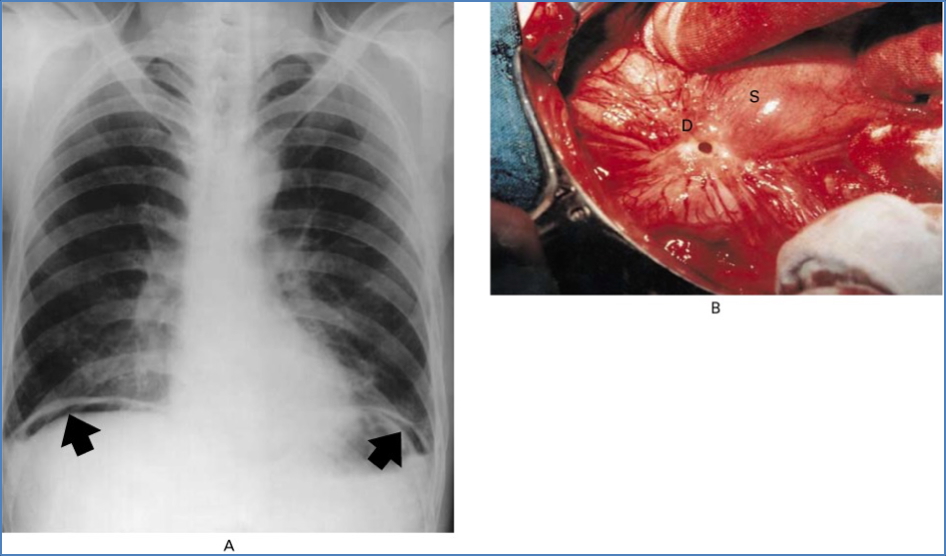

- Perforation

- Perforation → shock, peritonitis, possible pancreatitis

- High risk of perforation and bleeding